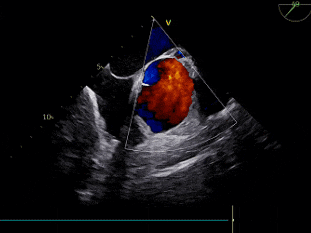

术前超声

超声心动图

主动脉中度狭窄并重度反流

TEE

左室短轴切面见二叶瓣畸形、长轴切面见重度反流。